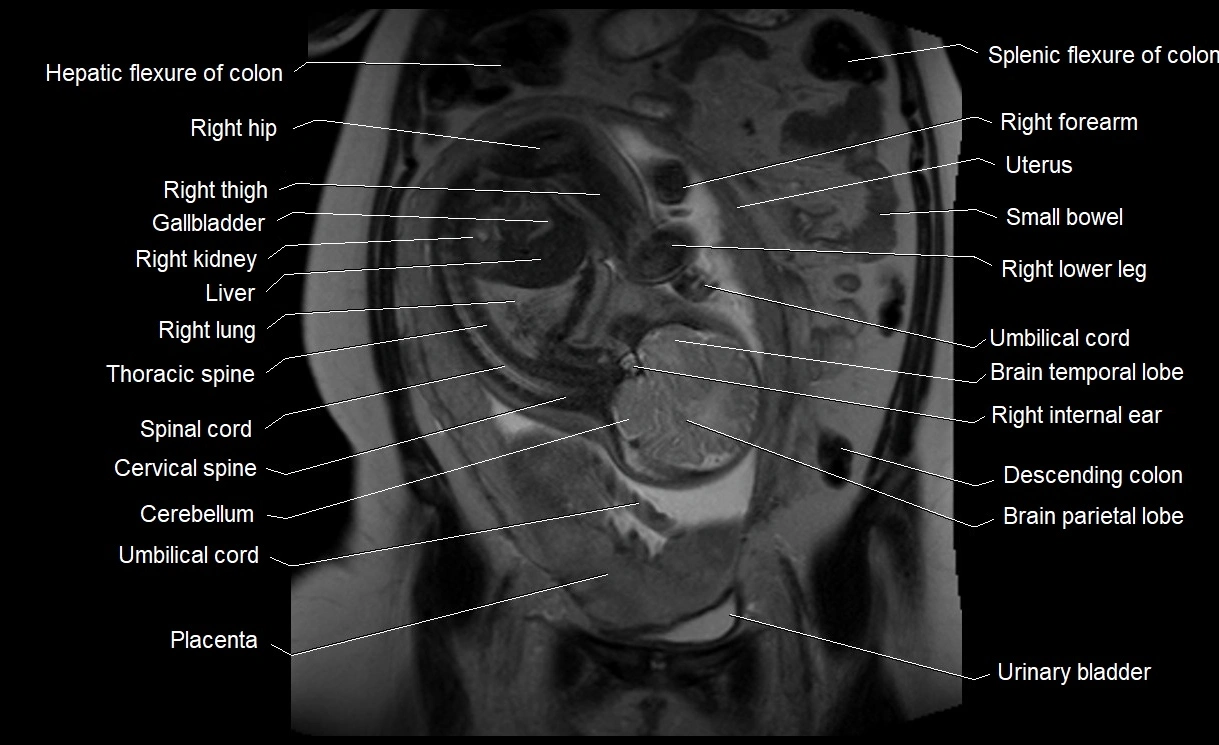

Relations

• Enclosed within the amniotic sac, bounded by the amnion and chorion

• Surrounds and cushions the developing fetus

• In continuity with maternal circulation through placental and transmembrane exchanges

MRI Appearance

T2 HASTE (T2 GRE):

• Amniotic fluid shows very bright hyperintense signal

• Provides natural contrast against fetus and placenta

• Small particles (vernix) may appear as scattered hypointense foci within bright fluid